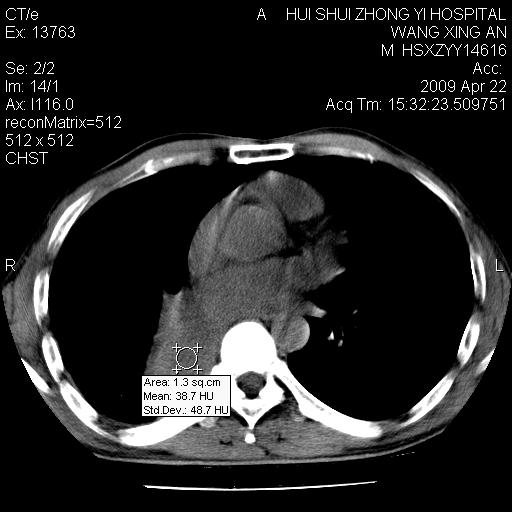

标题: CT19534:患者男、46岁咳嗽、胸痛半月。 [打印本页]

标题: CT19534:患者男、46岁咳嗽、胸痛半月。

考虑---右肺中心型肺癌继发下叶不张,少量胸水。

支持右侧中央型肺ca并右下肺不张、右侧胸腔少量积液。

1、右下肺中央型肺癌并右肺转移,右肺下叶不张。(右肺有结节影)。

2、右中上肺陈旧性肺结核(因为大多为纤维灶)。

3、右侧胸腔积液。

1、右下肺中央型肺癌并右肺转移,右肺下叶不张。(肿块围绕右肺下叶支气管生长,致管腔闭塞右肺下叶不张;右肺有结节影)。

2、右侧胸腔积液。

3、右中上肺陈旧性肺结核(右肺见纤维化病灶及点状钙化)。

1)右肺中间段支气管癌并右肺下叶肺不张。2)右肺上叶、两肺下叶背段感染性病变。3)右侧少量胸腔积液。